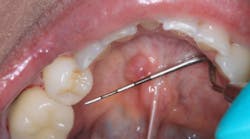

Clinical assessment reveals a red, tissue-colored, raised, fluctuant mass on the left side of the lingual frenum, in the area of the submandibular gland duct. There is a slight tenderness to palpation with some firmness to the lesion overall. The mass measures approximately 4 mm x 5 mm in length (see photos below).